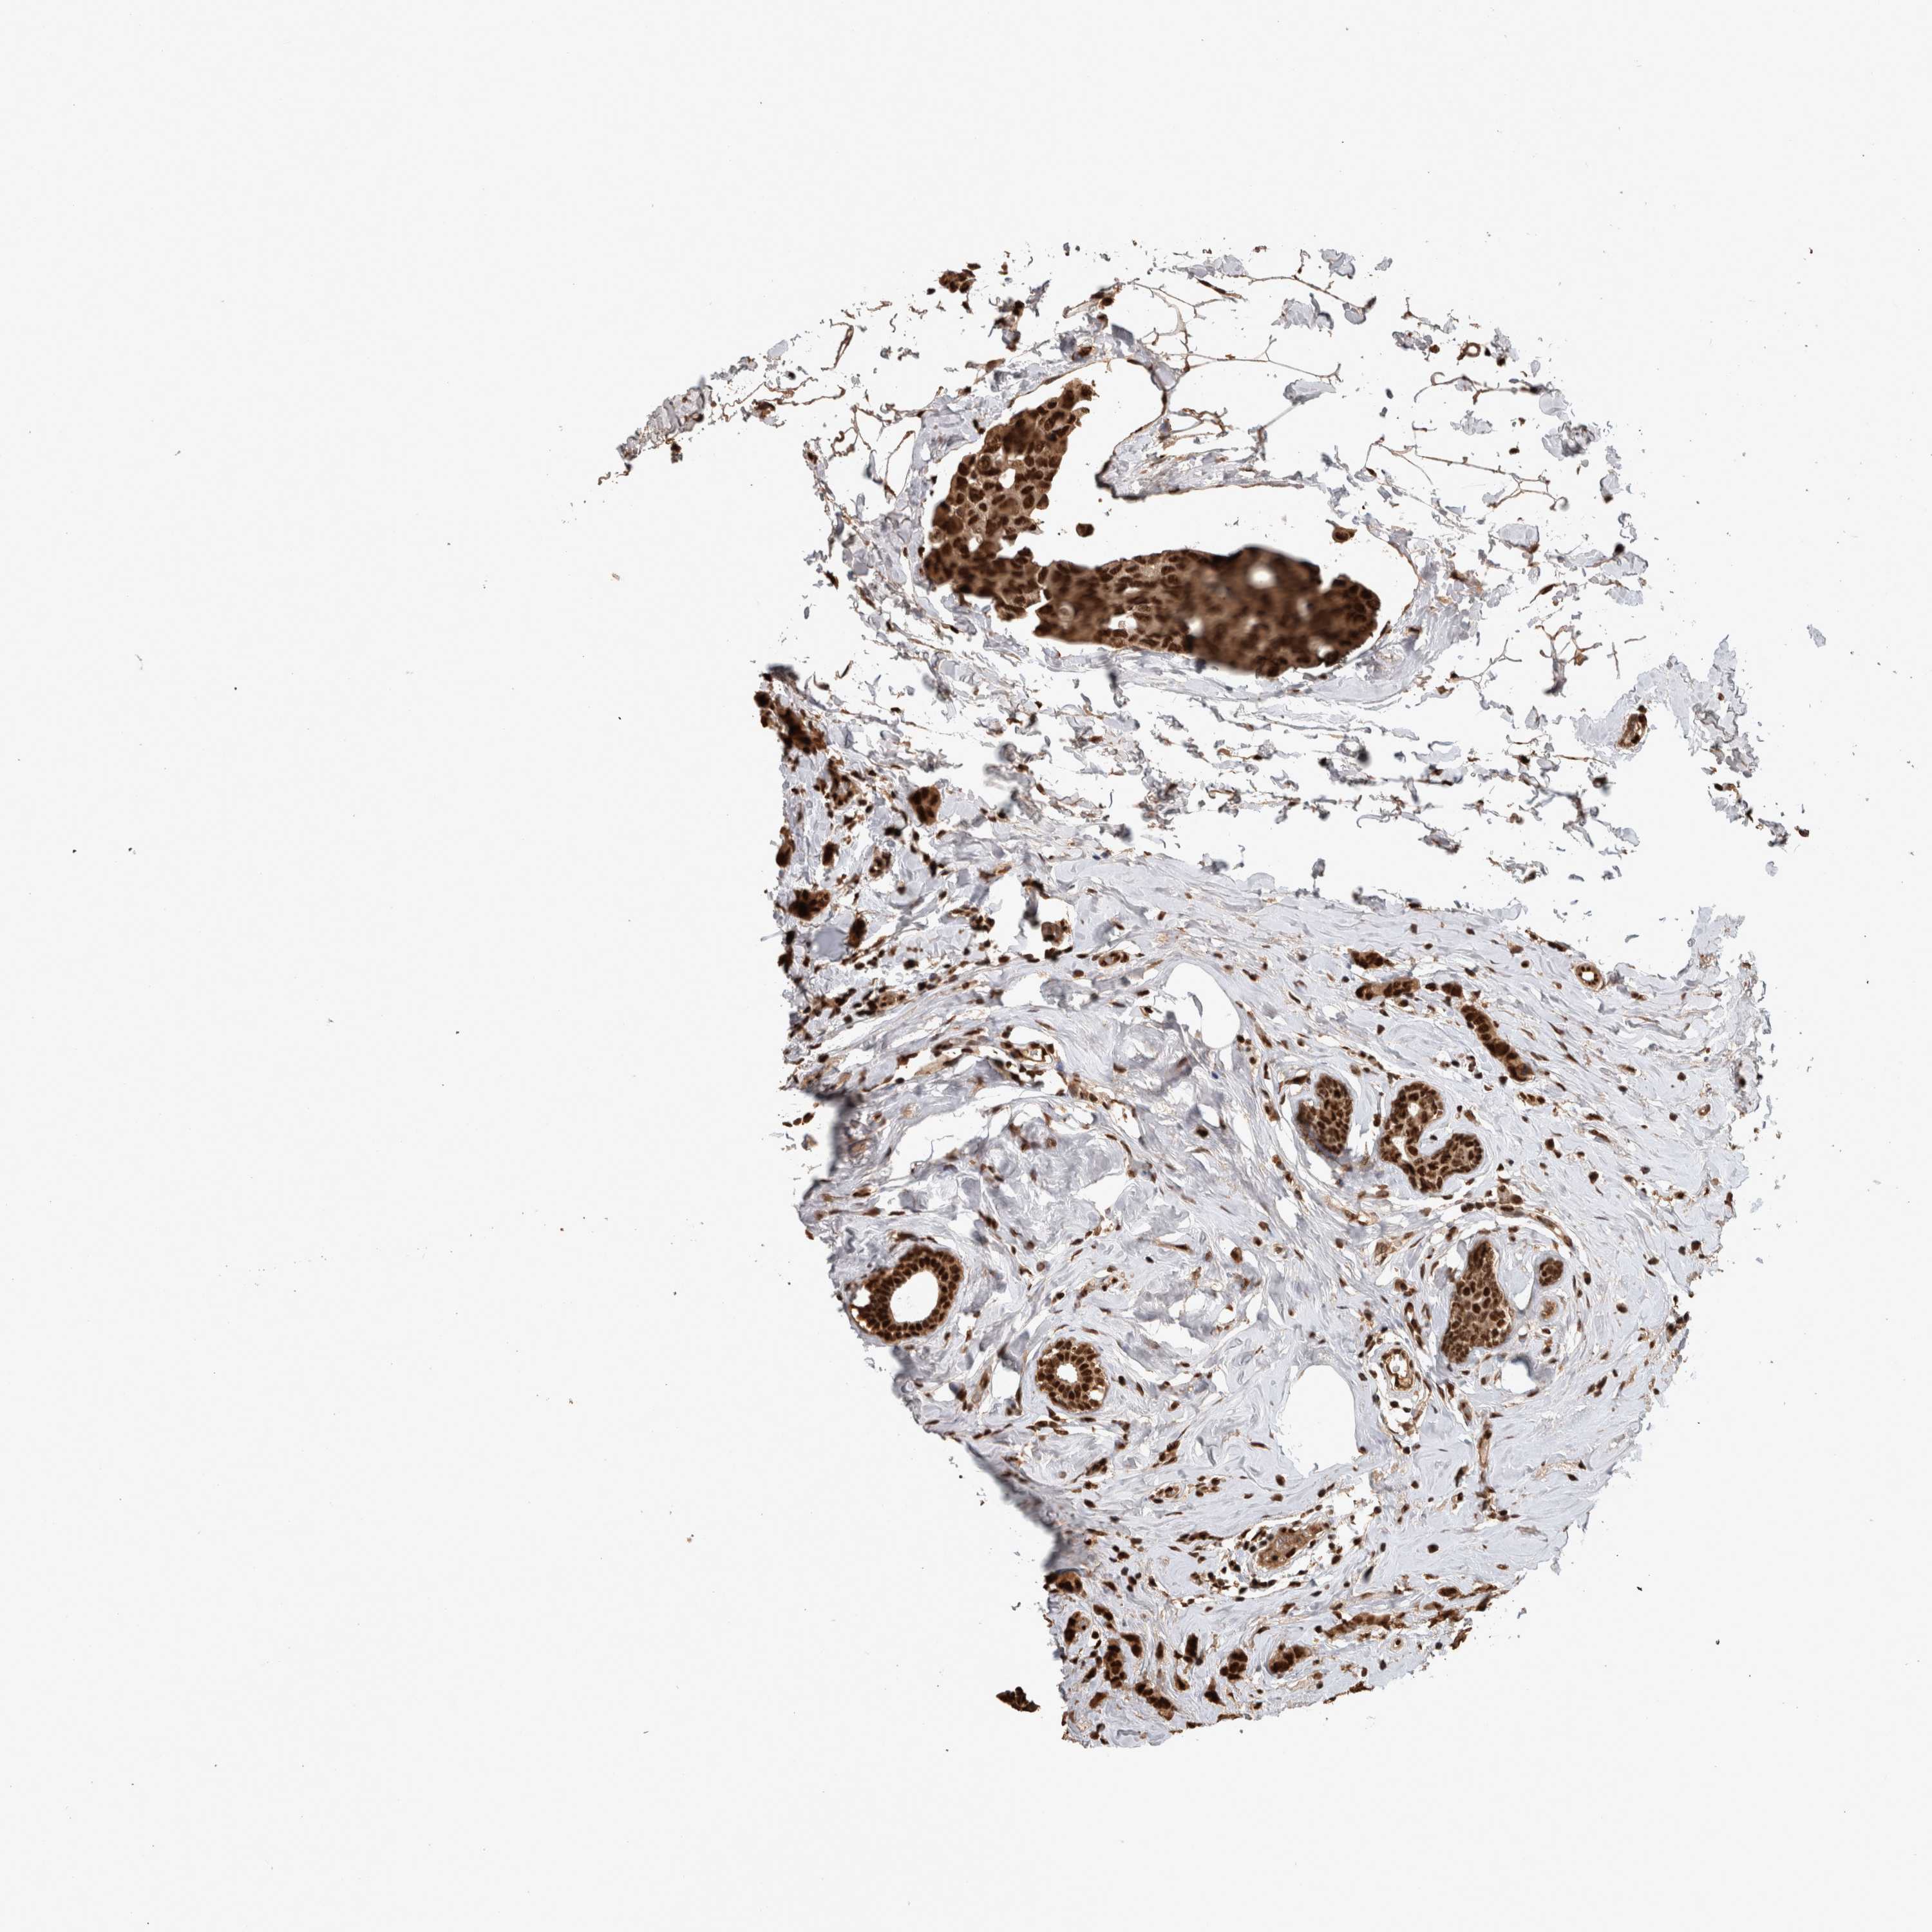

BRCA TCGA BRCA VALIDATION PROTEIN EXPRESSION

Breast cancer

Human cancer